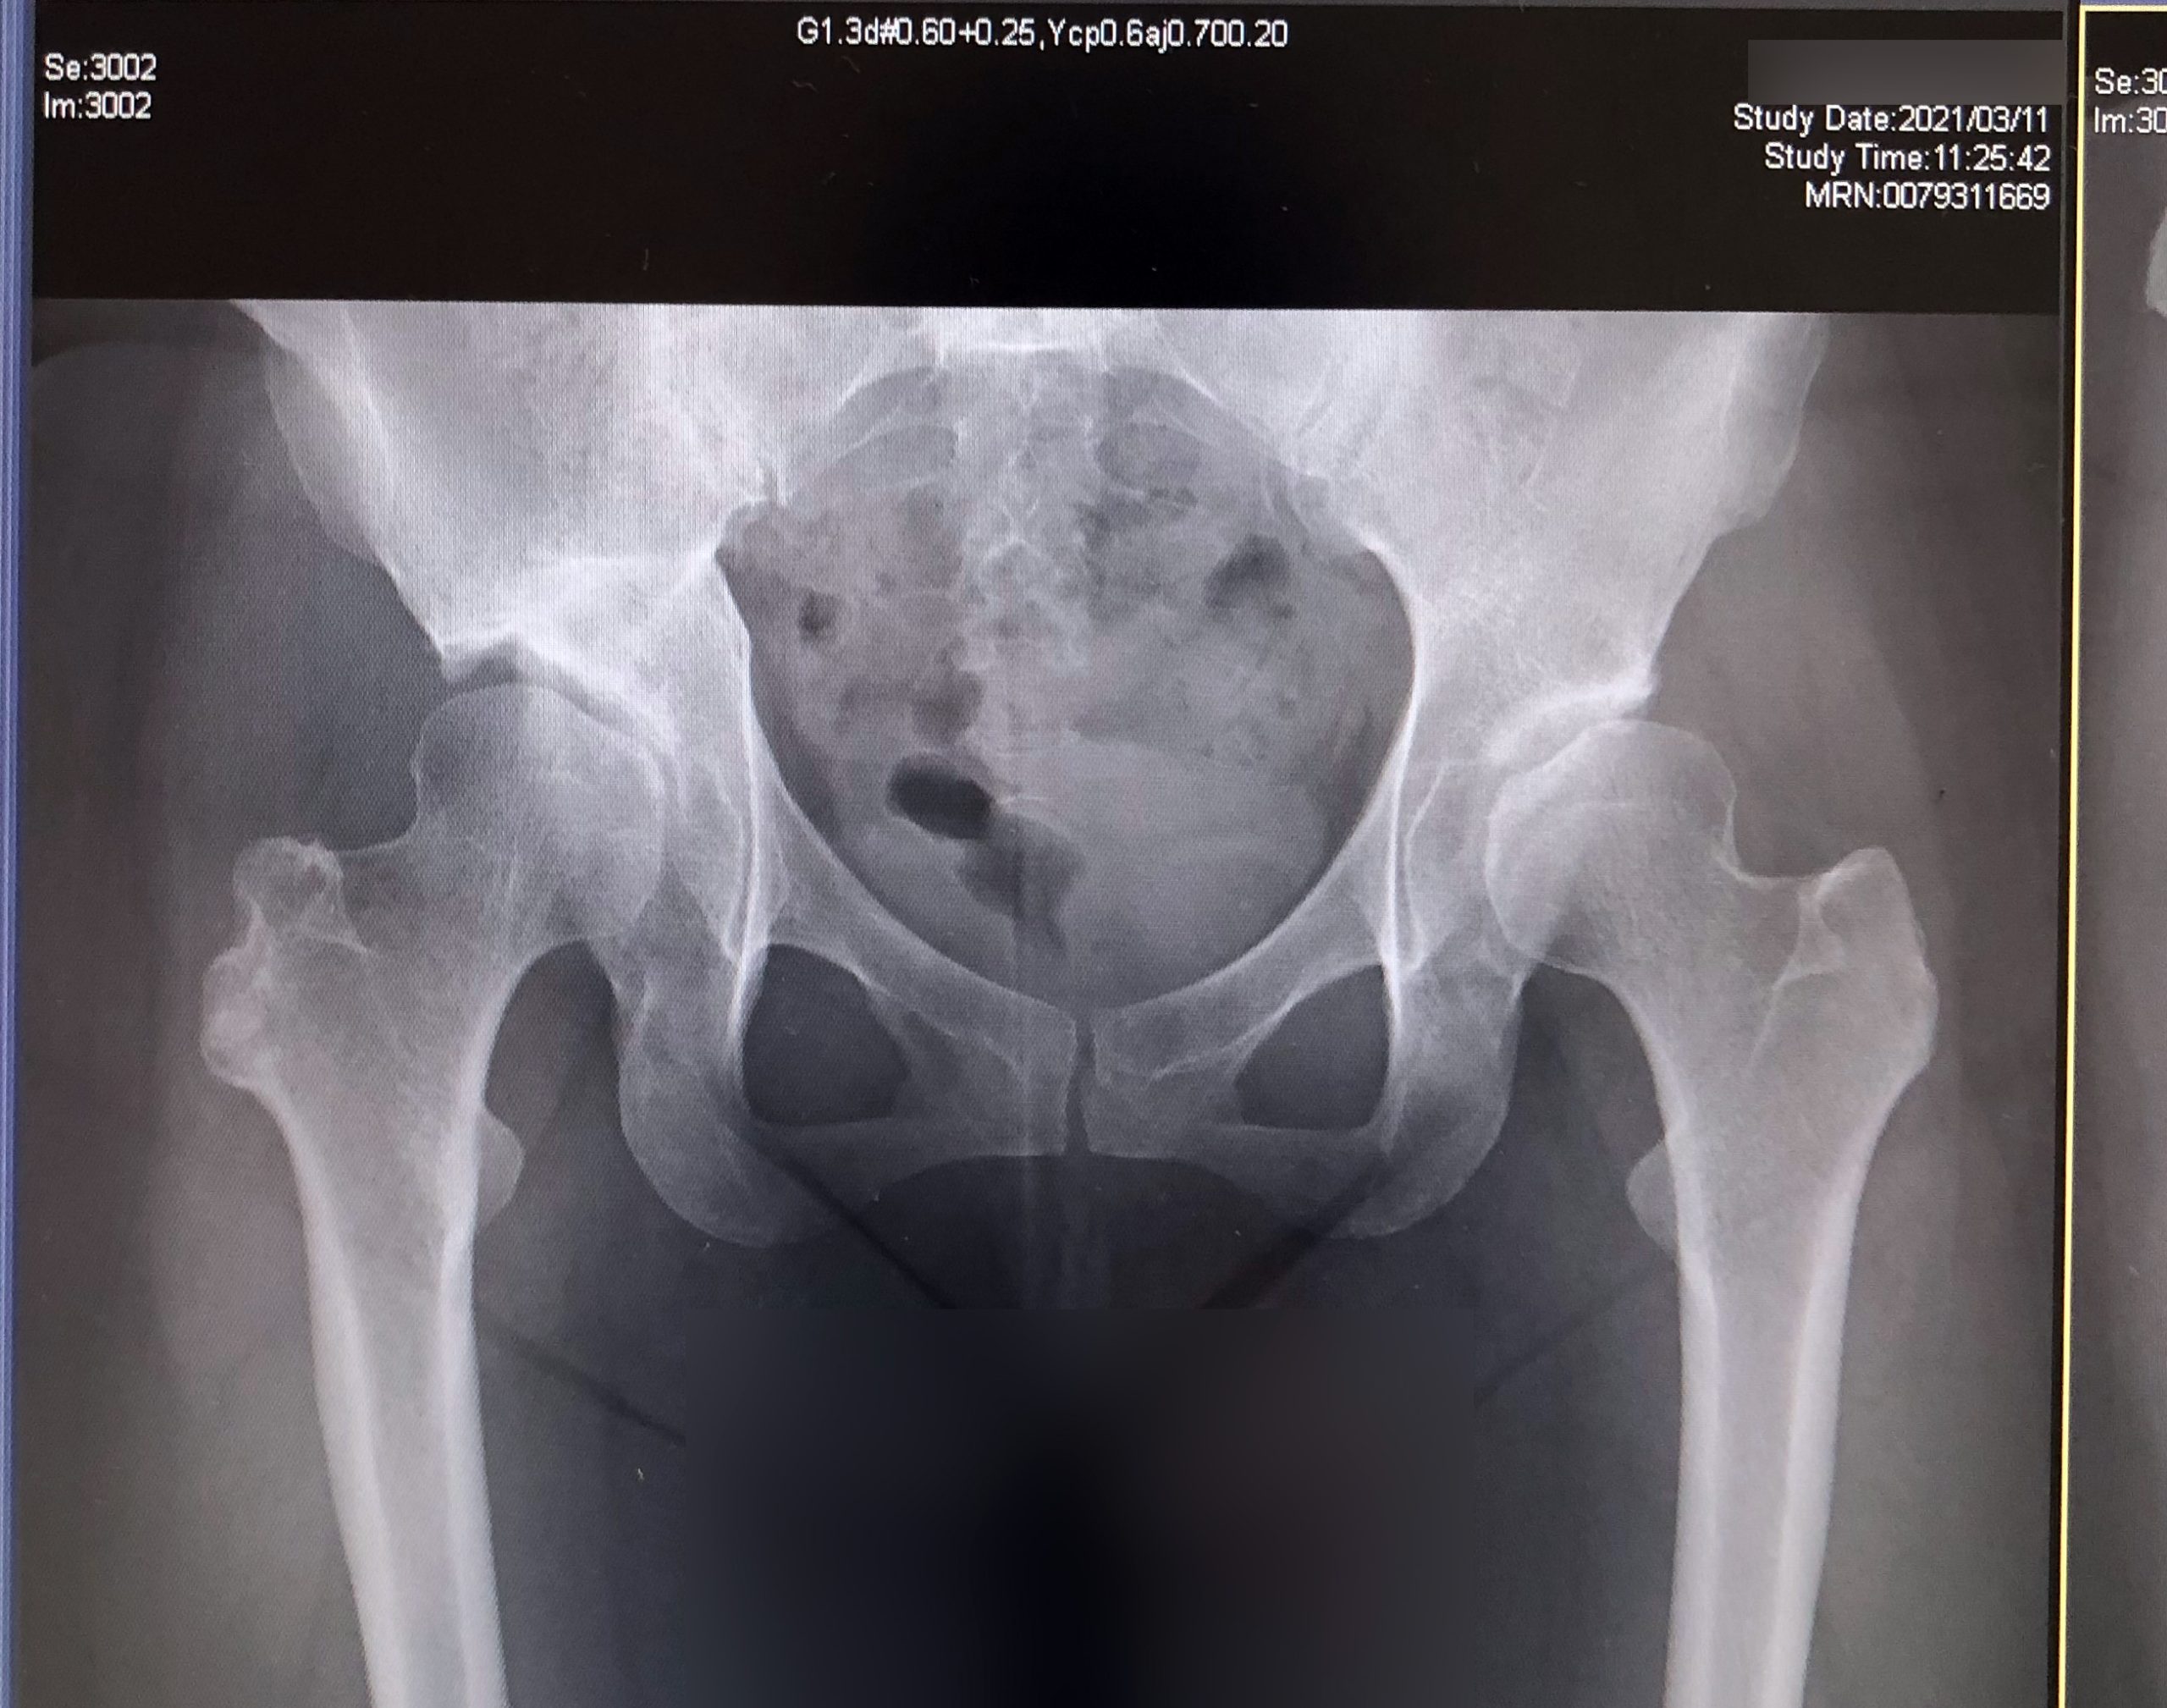

変形性股関節症-定期検診2021:骨切り手術から16年目

2021/3/11東京医科歯科大学病院

2020年との比較